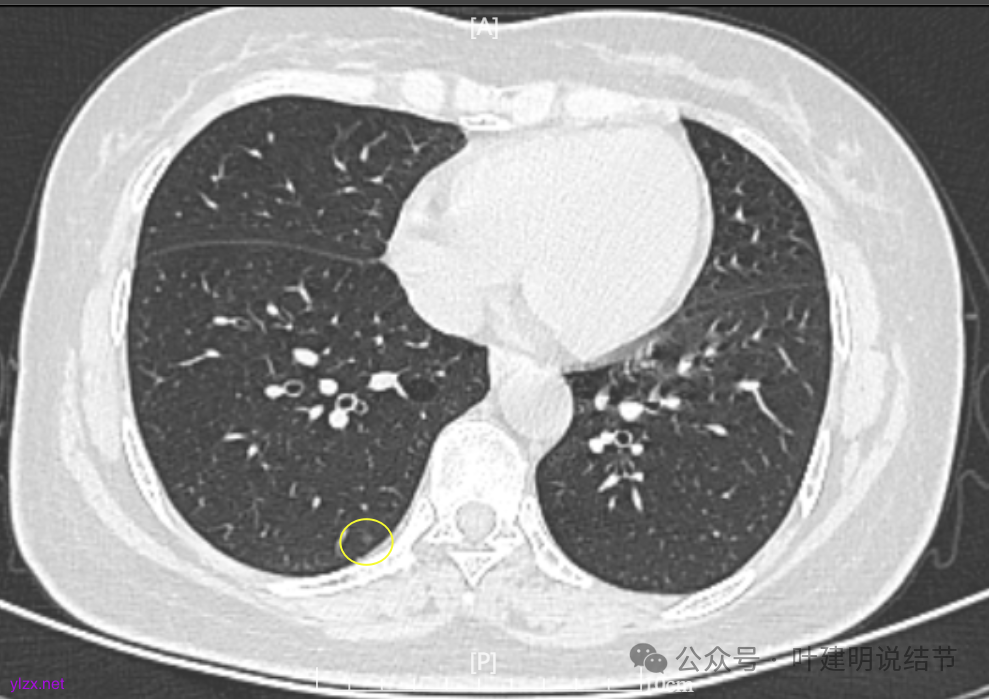

7.2022年11月1日B医院复查ct,显示肺结节0.89*0.51cm。其余变化不大。

8.2023年1月B医院复查ct,显示最大肺结节0.85*0.73cm,其余变化不大。

9.2023年4月复查ct,显示最大肺结节0.79*0.72。2023年3月短暂去某地疗养一月。

10.2023年11月28日复查CT,显示最大结节0.8*0.7cm。

我们发现其实各病灶与三年前比说不上显著进展。